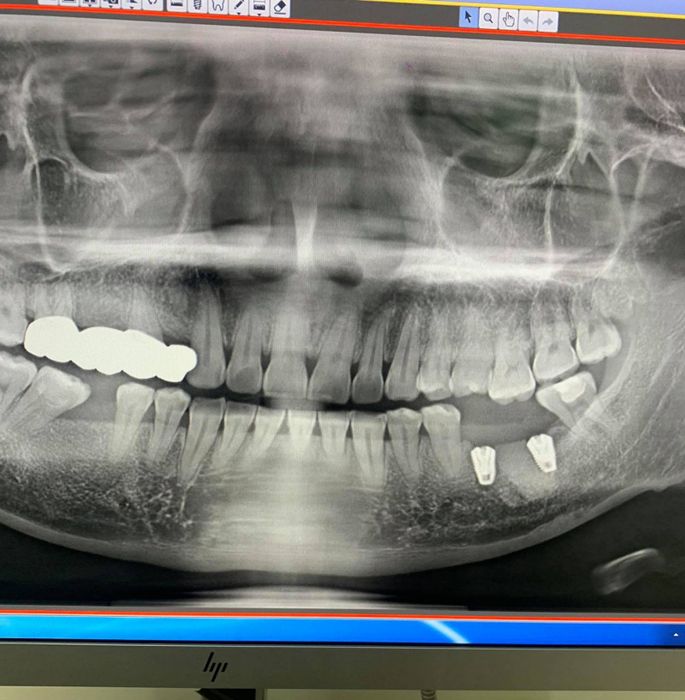

- Chụp phim X-quang: Kiểm tra xương hàm, xác định vị trí cấy ghép trụ implant.

Nha Khoa Minh Nhơn sử dụng công nghệ CAT Scans cắt lớp 3 chiều để nghiên cứu xương hàm và các cấu trúc xương lân cận với độ chính xác cao. Việc ứng dụng công nghệ hiện đại giúp quy trình điều trị an toàn, hiệu quả và nhanh chóng hơn, đồng thời giảm thiểu xâm lấn không cần thiết và sai sót chủ quan.